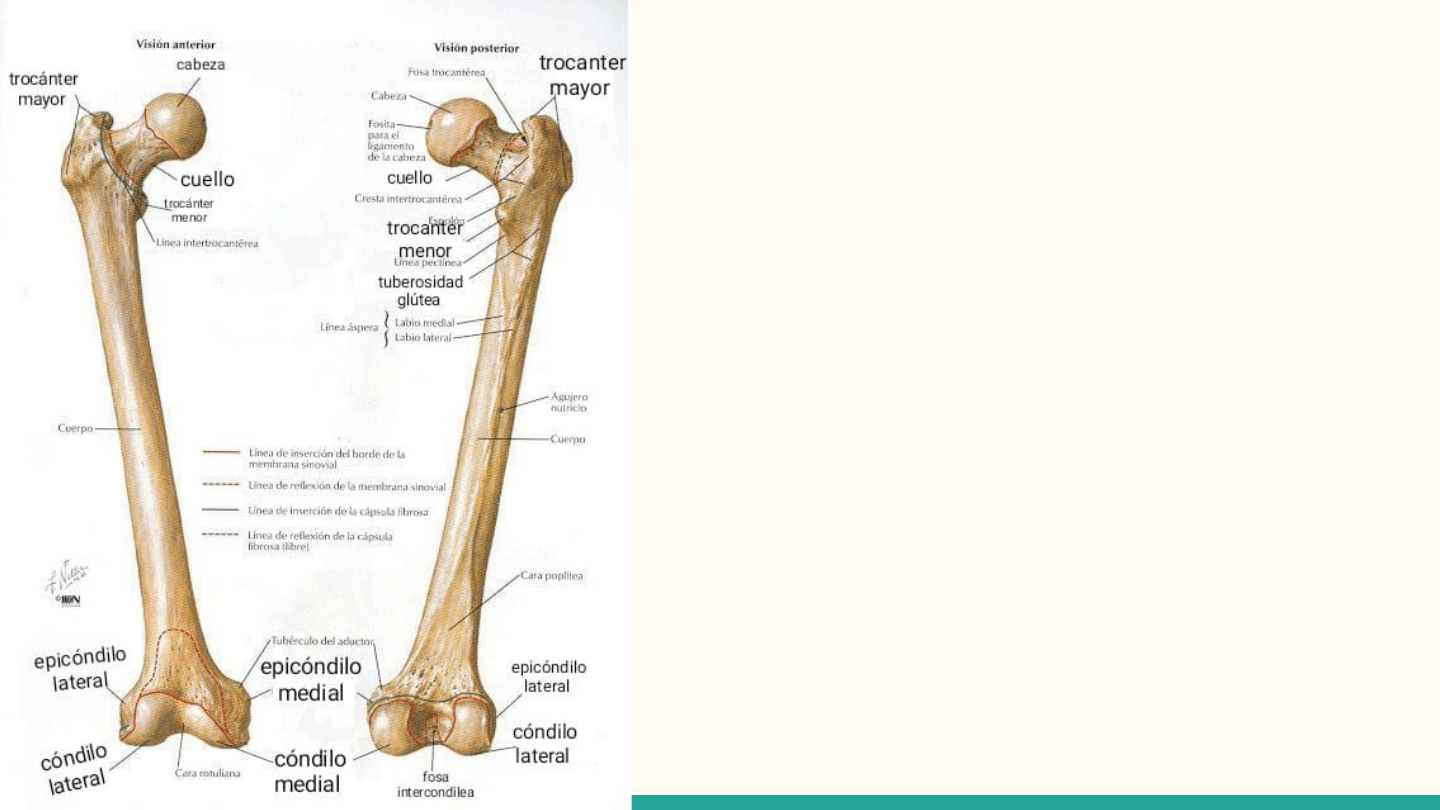

FÉMUR

Hueso largo que articula

superiormente con el hueso coxal hacia

superior y con la tibia inferiormente,

se ubica de forma oblicua, la cual está

más acentuada en la mujer que en el

hombre, ya que la pelvis de la mujer es

más ancha y los acetábulos están más

separados.